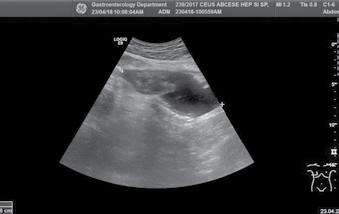

Angiosarcomul hepatic – prezentare de caz

As. Univ. Dr. Ana Maria Ghiuchici, Conf. Univ. Dr. Mirela Danilă, Conf. Univ. Dr. Maria Cornianu, Dr. Nicoleta